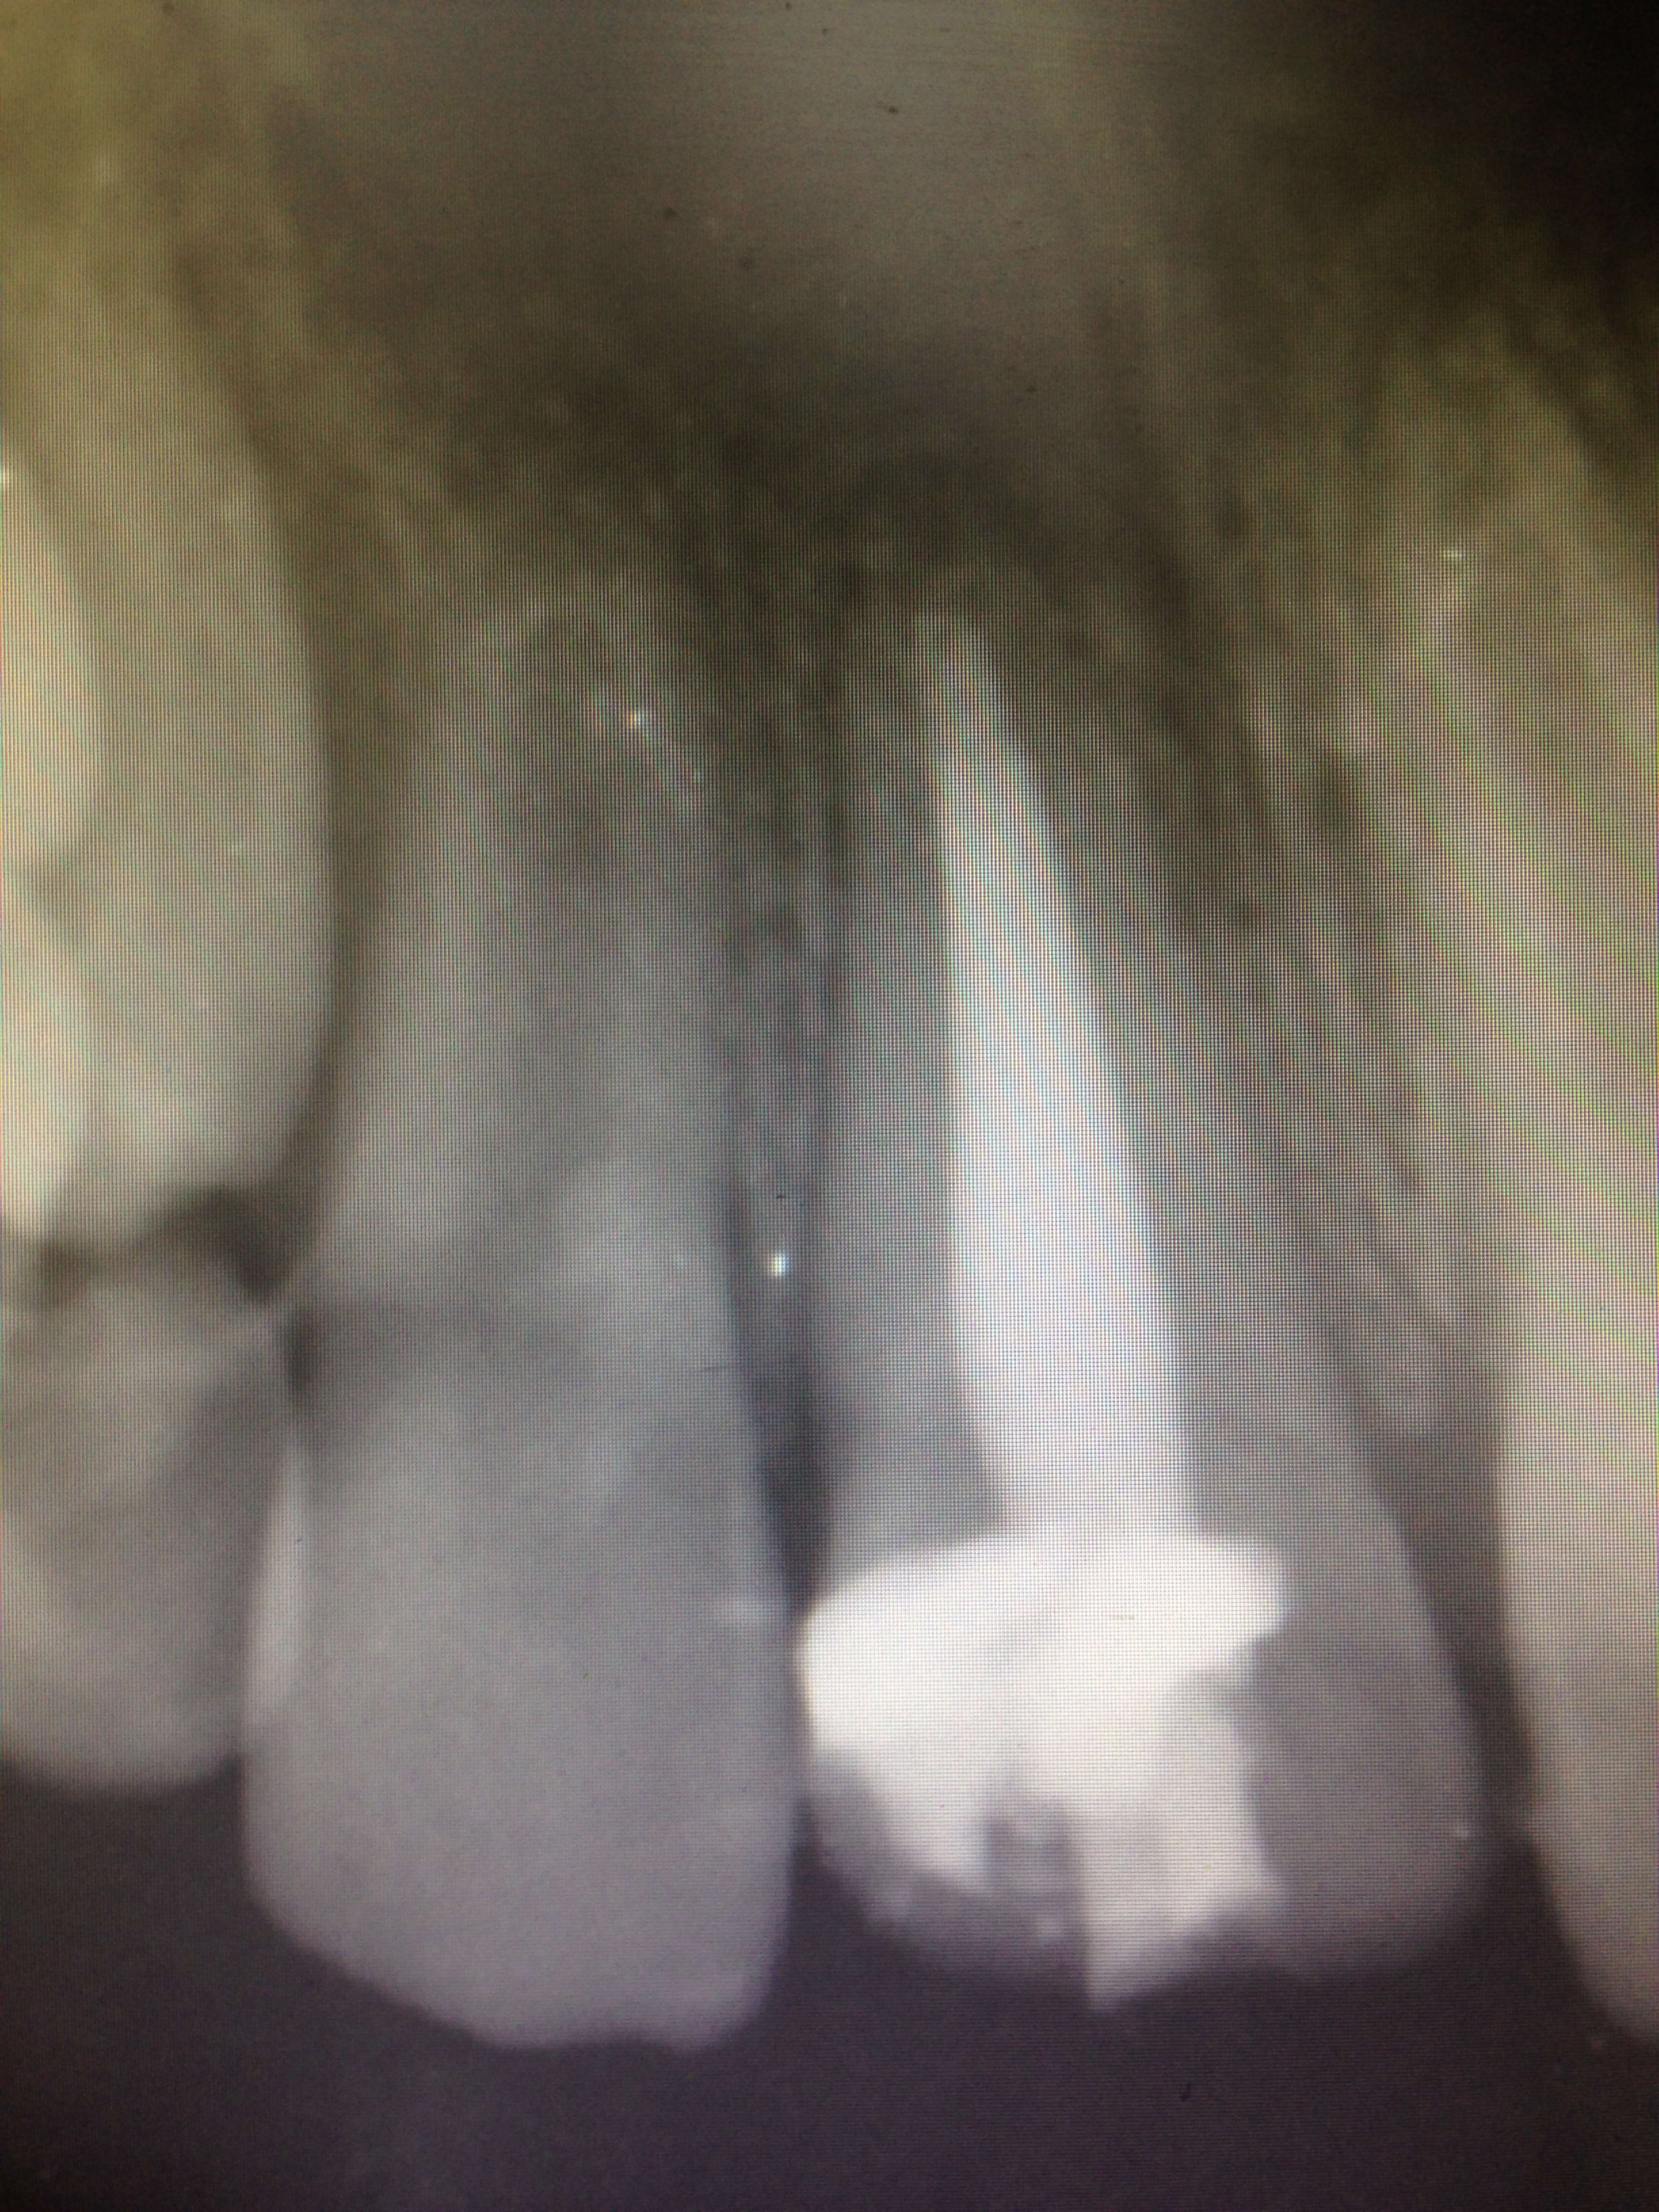

j'ai eu ce petit patient ce matin ... assez compliqué pour le traiter car ne tient pas en place. Enfin bref passons . Je lui ai mis des cales en bouche pour qu'il ne me les brise pas trop.J'ai instrumenté jusqu'à l'apex puis obturé. Biodentine Et gutta. Le problème c'est que la biodentine n'est pas tout à fait à l'apex . J'étais en fait persuadé d'avoir assez poussé ma biodentine Et donc j'ai pas fait de radio de contrôle avant de mettre ma gutta .... avis des pros de l'endodontie ? Dois je reprendre le traitement ? Ou je laisse Et j'attends ? C'est pas impossible que la biodentine sur les 2-3 derniers mm se soit dissoute un peu avec le sang Et du coup y a moins de radio opacité sur ces derniers mm?!

ca a un faible washout la biodentine, donc t'as pas assez poussé.

ok mais rien ne t’empêchais de remettre du Caoh et de recontrôler pendant 6-8mois car vu la radio je pense que l'apex n'est pas assez fermé et la lumière canalaire est aussi bien large, ce qui fait des parois radiculaire assez fragiles dans bien des cas.

maintenant, après avoir créer ton bouchon apical a la biodentine( est ce que le recul sur ce matériau est suffisant par rapport au MTA qui coute une blinde mais ça marche bien apparemment),tu peux aussi obturer la racine avec du cvi en remplissant le canal, puis tu introduit ta gutta "personnalisée" préalablement au canal. comme ça tu renforce les parois, et tu gardes une possibilité de mettre un tenon si nécessaire plus tard.